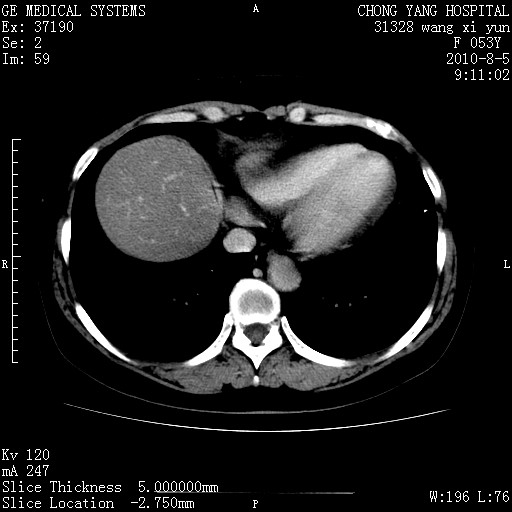

标题: CT28214:F41Y 血尿二十天,建议盆腔平扫加增强。

胆管细胞ca?

1)考虑肝左叶胆管细胞癌。2)脂肪肝。

支持胆管细胞ca。